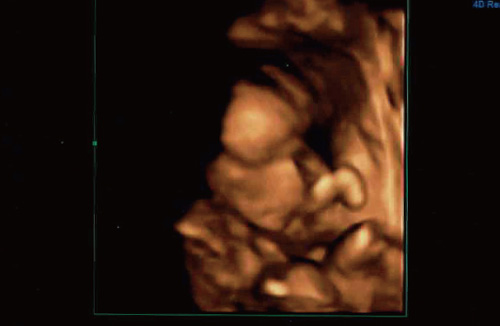

従来の超音波断層像の情報を集積し構築した疑似立体画像を高速演算処理することで疑似カラー立体アニメーション画像(動画)として描出したものが4Dイメージ画像です。

従来の断層像写真(所謂、白黒の平面画像)では一般の方にイメージしてもらうことが困難でしたが、4D画像によりお母さん方に(勿論お父さんにも)おなかの中の赤ちゃんの姿がわかりやすくなりました。

※この3D画像を動画にしたものが4Dエコーです。